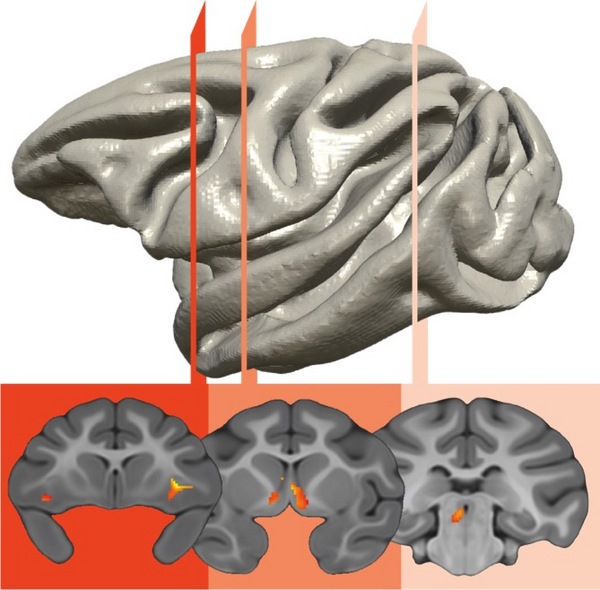

Un circuito cerebral que implica a tres regiones del cerebro es el responsable de la transferencia genética del temperamento ansioso. Fuente: Kalin Lab/Universidad de Wisconsin-Madison.

El estudio, del Departamento de Psiquiatría y el Instituto de Investigación HealthEmotions de la Universidad de Wisconsin-Madison (EE.UU.), ha demostrado cómo un circuito cerebral hiperactivo que incluye tres áreas del cerebro y que es heredado de generación en generación, puede sentar las bases para el desarrollo de la ansiedad y de los trastornos depresivos.

"El exceso de actividad de estas tres regiones del cerebro -prefrontal, límbica y cerebro medio- es una alteración cerebral hereditaria que está directamente relacionada con el riesgo posterior de desarrollar estos trastornos", dice el autor principal Ned Kalin, en la web de la universidad. El estudio se publica esta semana en las Proceedings of the National Academy of Sciences (PNAS), y sigue la línea de otros previos de este científico.

Durante este encuentro, se utilizaron métodos de imagen de uso común en los seres humanos (tomografía por emisión de positrones, PET) para identificar las regiones del cerebro en el que el aumento del metabolismo predecía el nivel de ansiedad de cada individuo.

Curiosamente, el circuito cerebral que estaba correlacionado genéticamente con las diferencias individuales en ansiedad en la vida temprana involucraba a tres regiones del cerebro relacionadas con la supervivencia. Estas regiones están localizadas en el tronco cerebral, la parte más primitiva del cerebro; la amígdala, el centro límbico del miedo; y la corteza prefrontal, que es responsable del razonamiento de nivel superior y se desarrolla plenamente sólo en los seres humanos y sus primos primates.

Curiosamente, el circuito cerebral que estaba correlacionado genéticamente con las diferencias individuales en ansiedad en la vida temprana involucraba a tres regiones del cerebro relacionadas con la supervivencia. Estas regiones están localizadas en el tronco cerebral, la parte más primitiva del cerebro; la amígdala, el centro límbico del miedo; y la corteza prefrontal, que es responsable del razonamiento de nivel superior y se desarrolla plenamente sólo en los seres humanos y sus primos primates.

Sorprendentemente, estos estudios encontraron que era el funcionamiento de estas estructuras cerebrales -y no su tamaño- el responsable de la transferencia genética de un temperamento ansioso.